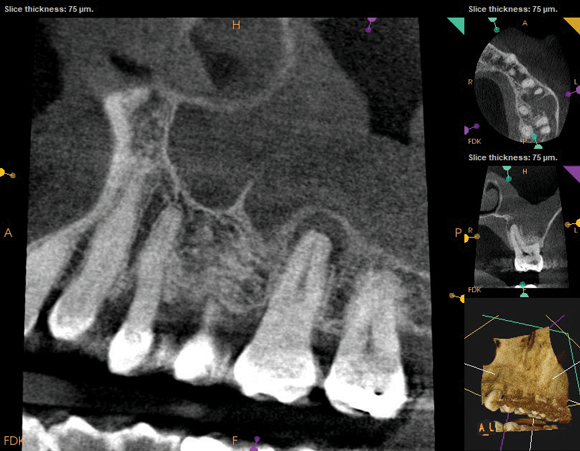

Periapical and CBCT imaging confirmed the presence of apical pathology, as well as a dramatic sinus communication with MSEO (Figure 1 and Figure 2). The diagnosis for tooth No. 13 was pulpal necrosis with asymptomatic apical periodontitis. NSRCT was completed (Figure 3). At the patient's 1-year follow-up appointment, tooth No. 13 remained asymptomatic, her sinusitis was resolved, and complete radiographic healing of both periapical pathology and the MSEO was noted (Figure 4).

As part of the endodontic evaluation, CBCT imaging showed periapical pathology associated with tooth No. 14 as well as significant MSEO (Figure 7 and Figure 8). Clinical testing confirmed the absence of a cold response but no tenderness to percussion or palpation. A composite buildup was in place, absent evidence of recurrent decay. Soft tissues were unremarkable.

Fig 7 and Fig 8. Preoperative CBCT scans showing evidence of periapical pathology on tooth No. 14 as well as communication with the adjacent maxillary sinus and associated mucositis. Fig 7: Sagittal view, buccal roots No. 14. Fig 8: Sagittal view, palatal root No. 14.

Fig 8. Preoperative CBCT scans showing evidence of periapical pathology on tooth No. 14 as well as communication with the adjacent maxillary sinus and associated mucositis. Fig 7: Sagittal view, buccal roots No. 14. Fig 8: Sagittal view, palatal root No. 14.

Figure 8